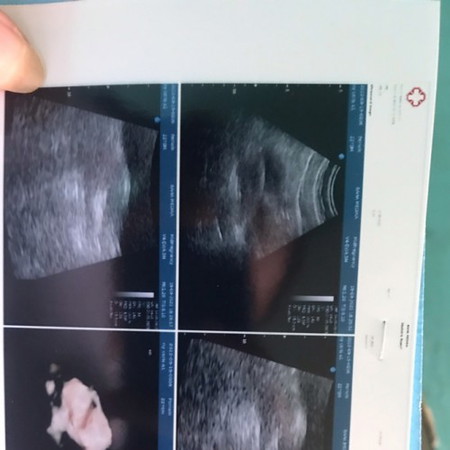

Udah 6 week tapi blm kliatan kantungnya. Gimana yaa mam

apa ga di jelaskan SMA dokternya bund, itu baru penebalan dinding rahim yg artinya akan ada tanda tanda penempelan embrio /janin, sabar dlu mungkin hamilnya masih terlalu muda Bund, tunggu sebulan lagi USG lagi insya Allah hasilnya udah ada kantung, janin dan djj nya. krna dlu aku jga gtu 5w4d USG blm trlihat Bru sprti itu, dan kembali lagi stlah sebulan alhmdulillah sudah ada .

Gpp sih Bun wajar saja , saya dulu 8week baru kelihatan janin ya , kalo Masi 6wekk wajar masih penebalan dinding rahim